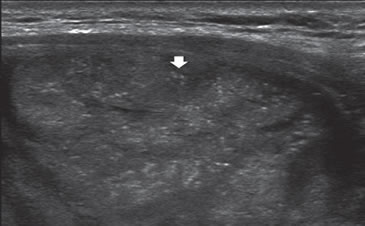

1. Tamaño

Los nódulos tiroideos se hacen palpables cuando alcanzan aproximadamente 10 mm de tamaño, dependiendo de su localización. Cuando la palpación era la principal manera de identificar nódulos, este diámetro era el límite para realizar una biopsia. Aunque las normas de la Asociación Americana de Endocrinólogos Clínicos (AACE) y la Asociación Americana de Tiroides (ATA) continúan usando 10 a 15 mm como el umbral práctico9,10 para seleccionar nódulos que necesitan de una PAAF, se ha demostrado que el tamaño no es un buen indicador para predecir malignidad. Son varios los trabajos que muestran que la prevalencia de cáncer es similar en nódulos mayores o menores de 10 mm11. La Sociedad de Radiólogos en Ultrasonido recientemente llegó al consenso de que, más que fijar un umbral de tamaño, debe usarse el aspecto ecográfico del nódulo como criterio de selección, tanto en el nódulo solitario como en la glándula multinodular4. En nódulos mayores de 10 mm no habría una diferencia significativa en el porcentaje de malignidad, aunque hay una tendencia que indicaría que la tasa de malignidad es más alta en nódulos mayores de 30-40 mm. El cáncer papilar menor de 10 mm se ha definido como microcarcinoma (Figura 1) y su frecuencia ha aumentado gradualmente en los últimos años12. Persiste el debate si este aumento es real o simplemente se debe al uso masivo de la ecografía cervical y la PAAF guiada por ecografía, lo que permite identificarlos precozmente. La presencia de múltiples nódulos no disminuye la probabilidad de cáncer tiroideo por paciente y el nódulo dominante por mayor tamaño no es necesariamente el que contiene el cáncer, ya que en aproximadamente un 30% el cáncer está en el nódulo no dominante4. Independiente del tamaño los nódulos casi completamente quísticos, sin otras características sospechosas, probablemente no requieren de biopsia.

Figura 1. Microcarcinoma de 8 mm.